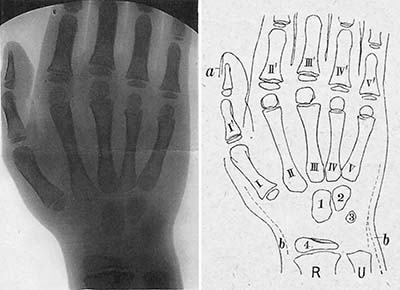

《1918-20-正常四肢骨のレントゲン写真図譜》

レントゲン写真図譜 (第一輯~第四輯)

藤浪剛一(朝香屋書店,1918-20)

図10. 10歳男児の右手.手根骨が3個骨化している.

図11. 16歳女児の左足関節.

藤浪は序文で,欧米のようなレントゲン図譜が本邦にはないことを憂い,かねてよりこれを企画していたものの,出版者が写真を鮮明に印刷する技術を持たず実現できなかったが,本書の出版社である朝香屋の主人がこれを引き受けてくれてようやく発刊できたと述べている.レントゲン図譜と銘打っているが,その内容は専ら四肢骨の正常像で,小児の骨化中心の出現に主眼が置かれている.藤浪は,ウィーン留学中に手根骨の骨化順序に関する論文を2篇著しており,その延長上にあるものと思われる.

第一輯から第四輯まで四分冊で,それぞれ手関節,肘・肩関節,足関節,膝関節の正常像を扱い,全58葉のレントゲン写真とそのスケッチが,小児から成人まで年齢順に供覧されている(図10,図11).写真の画質はかなり良好で,現在でも充分通用する解像度を備えている.

藤浪の著書で,放射線診断学領域を扱ったものは,本書の他には「内臓レントゲン診断学」および「れんとげん学」があるが,胸腹部の内臓疾患については詳細に書かれているものの,奇妙なことにそのいずれも骨格系の診断については全く触れていない.欧米では既にこの時期,骨折や骨端症の画像所見が数多く報告され,教科書も書かれていることを考えると疑問に思うところであるが,藤浪は特にこの点について言及していない.その意味で本書は,正常像のみであるが骨格系のレントゲン像を記載した唯一の著書である.